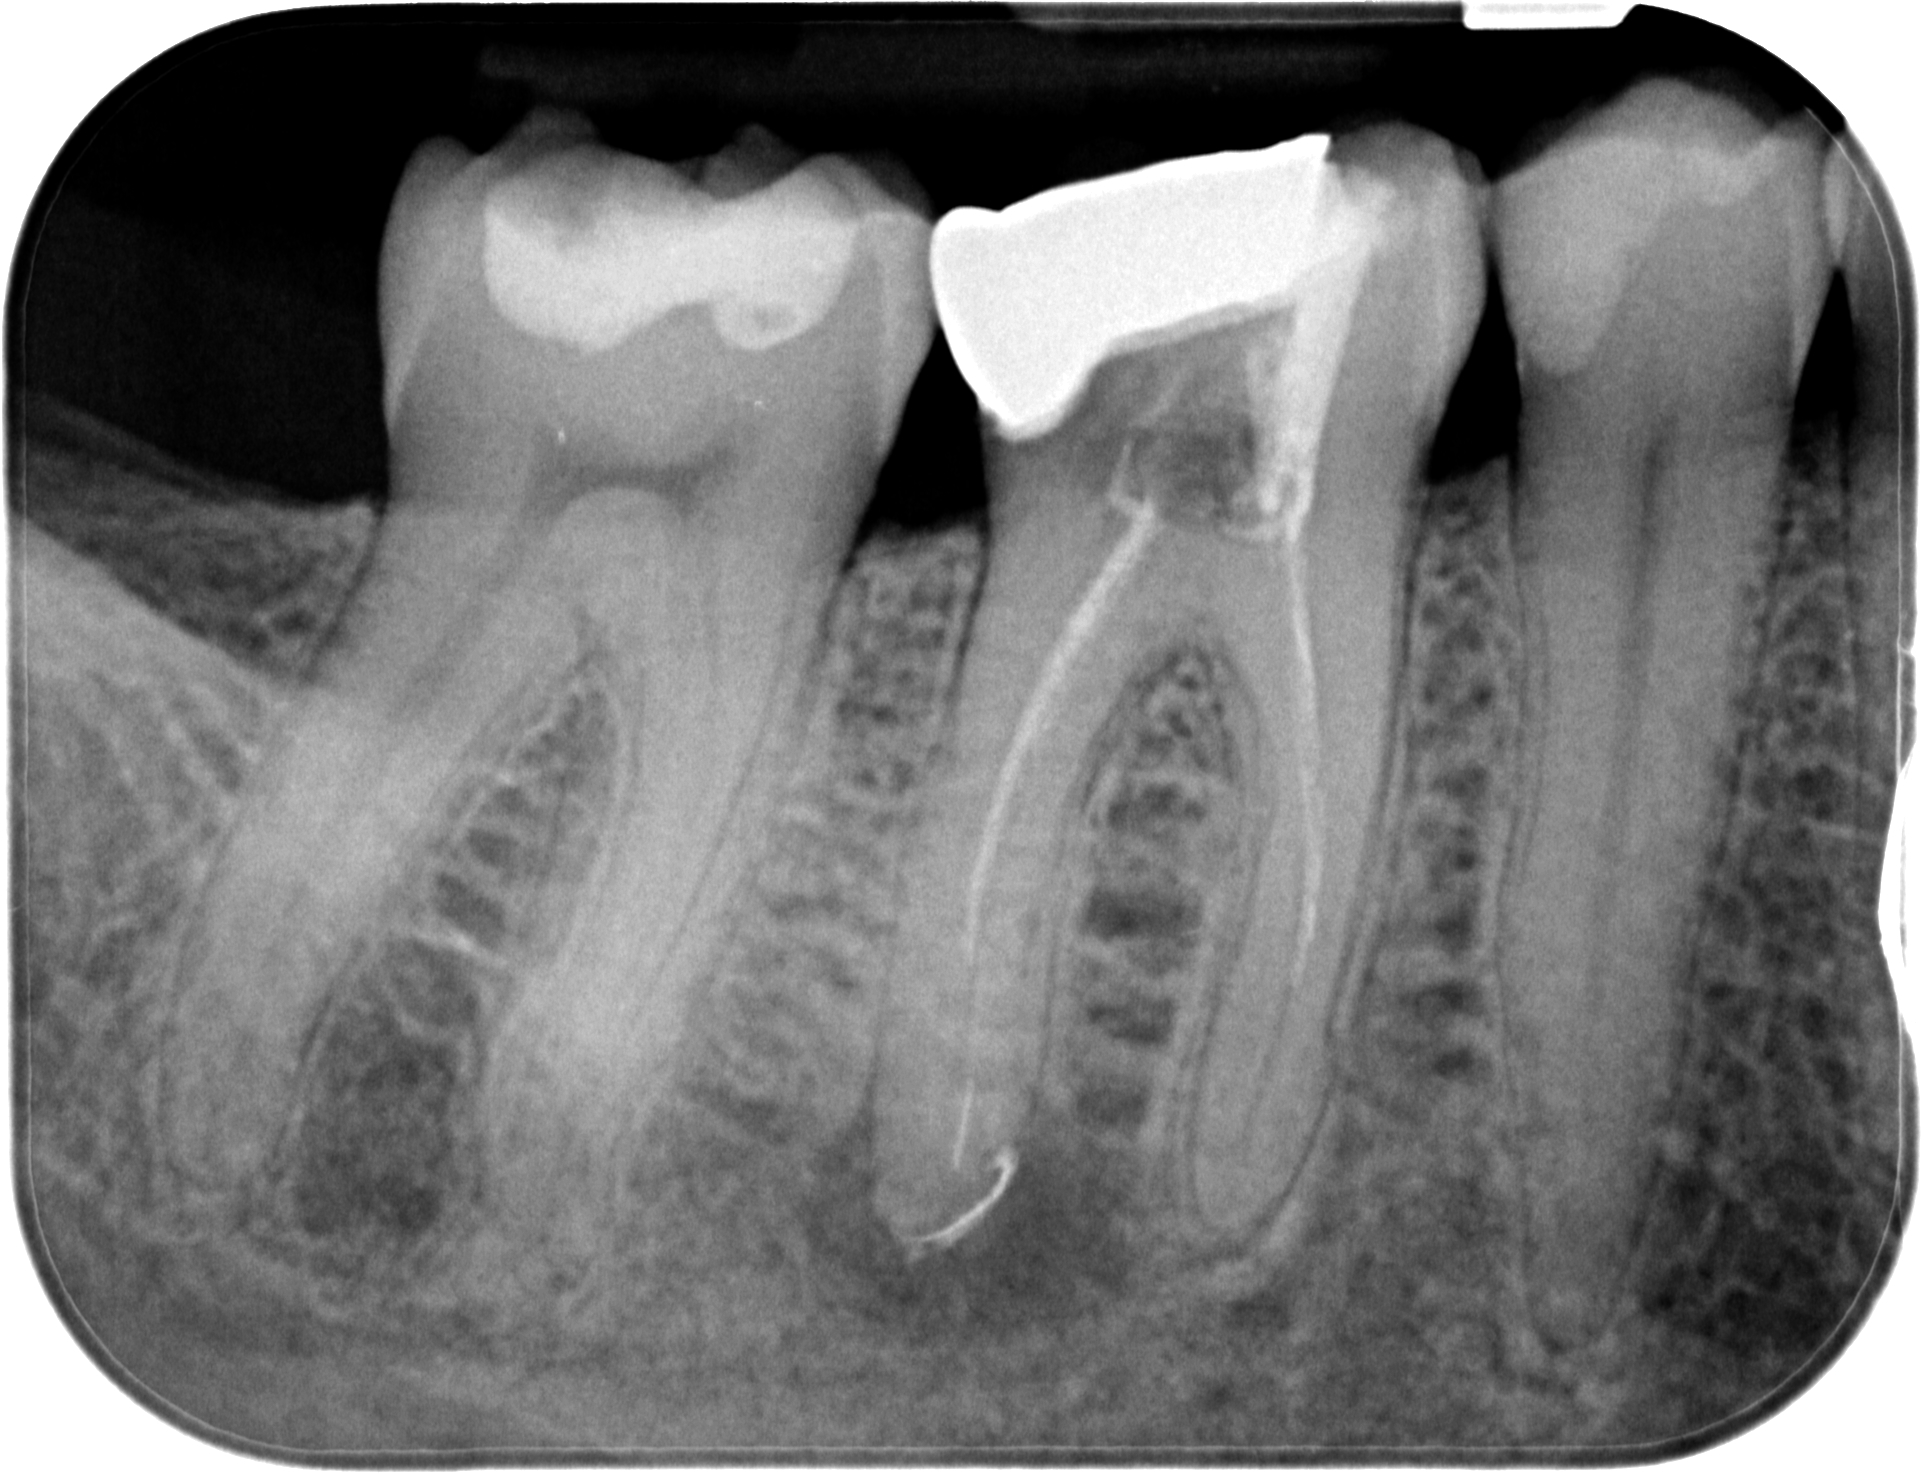

25.03.2021 Patientin DW, geb. am 12.04.1968, Zahn 46,26, WF Revision, WF-Kontrolle minimal 20 Monate post WF